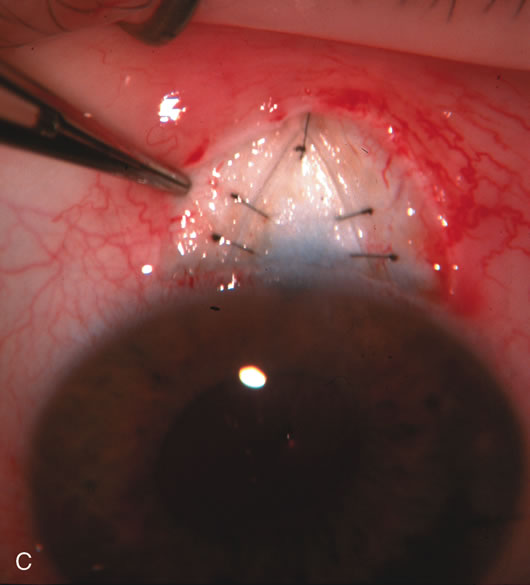

Fig. 1. The anatomic advantage of small incision cataract surgery for the glaucoma patient. A. Long-term bleb function with a large cataract incision is difficult to achieve with either ECCE-trabeculectomy or trabeculectomy followed later by ECCE. This bleb failed to form sufficiently when combined with large incision ECCE. The inflammation, bleeding, and long-term wound healing with stimulation of fibroblasts associated with this technique are more likely to cause bleb failure. In addition, the increased iris manipulation necessary to deliver the nucleus and subsequent iris repair adds to the long-term breakdown of the blood aqueous barrier. B and C. Two-site phacotrabeculectomy has the advantage of small incision cataract surgery combined with separate site trabeculectomy. The incision size is one third the size of the standard ECCE. The inflammation is less severe, and cataract wound healing is confined to the temporal area. Visual rehabilitation with phacoemulsification and foldable IOL is much faster. Phacoemulsification allows successful lens extraction even in the unfriendly environment of a smaller pupil compared with ECCE. The trabeculectomy is performed in an entirely different site, well away from the wound healing associated with temporal phacoemulsification. The likelihood of this filter functioning long-term is greater than with ECCE-trabeculectomy. D. The surgeon also has the option of single-site phacotrabeculectomy with foldable IOL. Both the lens extraction and trabeculectomy are performed through one small 3.5-mm limbal incision.

Fig. 3. Partial bleb failure following clear corneal phacoemulsification with foldable IOL. A. Preoperative bleb appearance prior to temporal lens extraction. Preoperative IOP was 12 mm Hg on no antiglaucoma medications. Time from 5-FU trabeculectomy surgery to lens extraction was one year. B. Bleb appearance 2 months after clear corneal cataract surgery with topical anesthesia. Following lens extraction, increased vascularity was noted along with decreased size of the filtering bleb. IOP increased to 20 mm Hg as early as 2 weeks after surgery, necessitating topical antiglaucoma therapy. C. High magnification view of bleb before lens extraction demonstrates diffuse pale bleb. D. High magnification view of bleb 2 months after surgery. There are vessels surrounding the nasal side of the bleb and the overall bleb size is smaller.